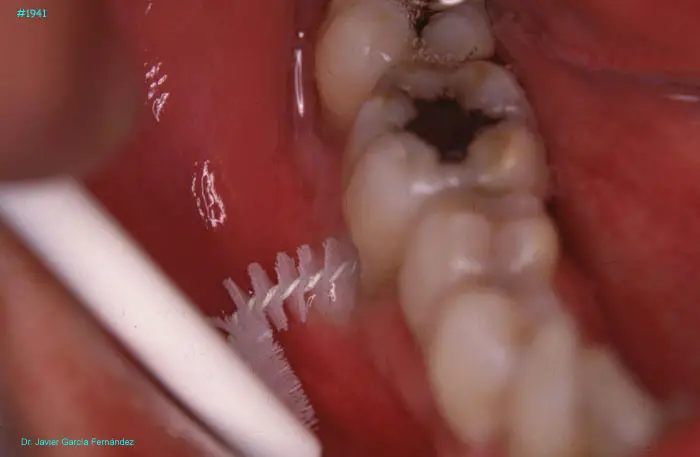

image 88